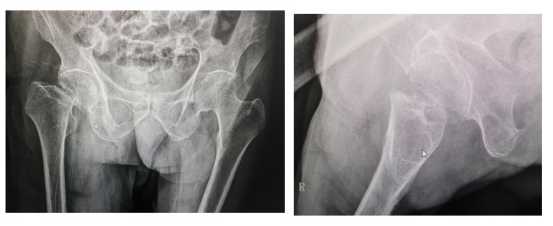

2022年2月24日,突如其来的意外使得邱金福老爷子失去了行走的能力,为求治疗,前往相关医院就诊,因患者年高,108岁,考虑到风险问题,所寻求医院拒绝为其进行治疗。最后辗转来到江西省中医院,来到我院关节骨科后,由涂宏主任接诊并收入我院行住院治疗。完善检查检验,影像学资料显示:右侧股骨颈骨折,符合手术指征。